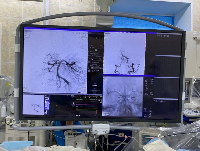

Мобильный рентгенаппарат + оцифровщик. Получение рентгеновского изображения на экране ноутбука. Вариант за 1,4 миллиона рублей под ключ.

Магнитно-резонансная томография (МРТ):один из самых эффективных методов диагностики заболеваний